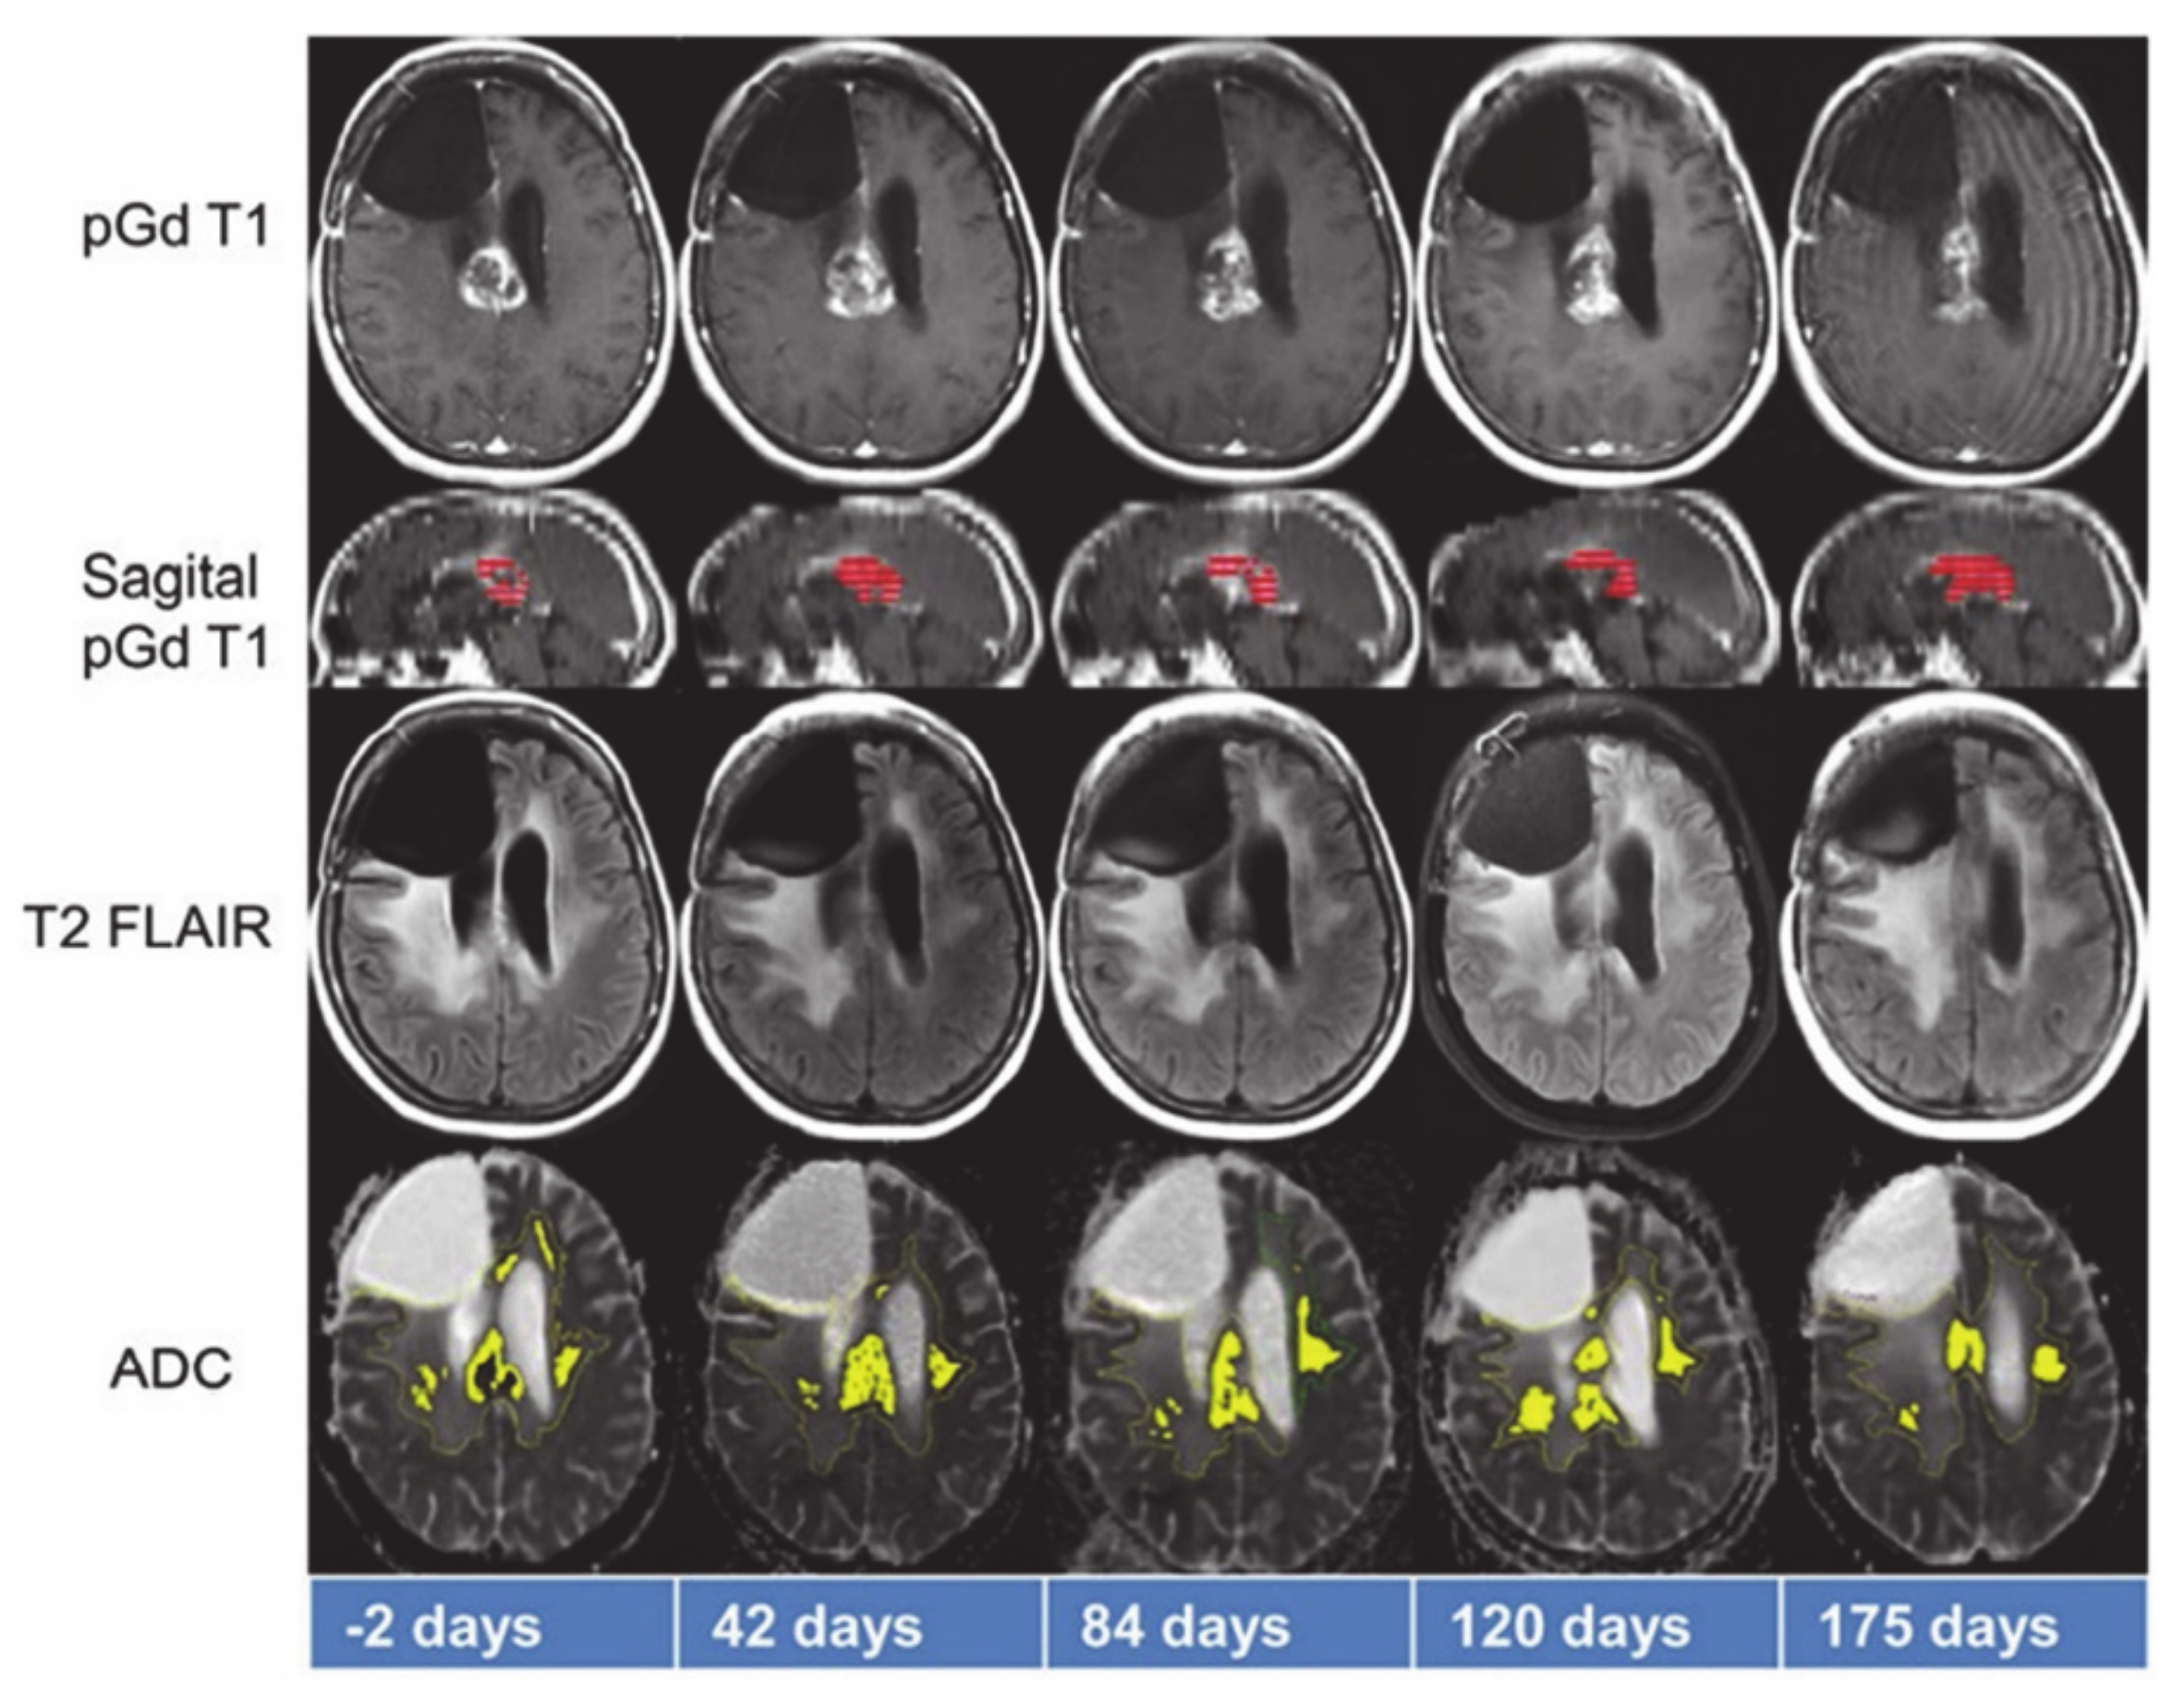

- Brahm, C.G.; Hollander, M.W.D.; Enting, R.H.; De Groot, J.C.; Solouki, A.M.; Dunnen, W.F.A.D.; Heesters, M.A.A.M.; Wagemakers, M.; Verheul, H.M.W.; De Vries, E.G.E.; et al. Serial FLT PET imaging to discriminate between true progression and pseudoprogression in patients with newly diagnosed glioblastoma: A long-term follow-up study. Eur. J. Nucl. Med. Mol. Imaging 2018, 45, 2404–2412. [Google Scholar] [CrossRef]

- Ceschin, R.; Kurland, B.F.; Abberbock, S.R.; Ellingson, B.M.; Okada, H.; Jakacki, R.I.; Pollack, I.F.; Panigrahy, A. Parametric Response Mapping of Apparent Diffusion Coefficient as an Imaging Biomarker to Distinguish Pseudoprogression from True Tumor Progression in Peptide-Based Vaccine Therapy for Pediatric Diffuse Intrinsic Pontine Glioma. Am. J. Neuroradiol. 2015, 36, 2170–2176. [Google Scholar] [CrossRef]